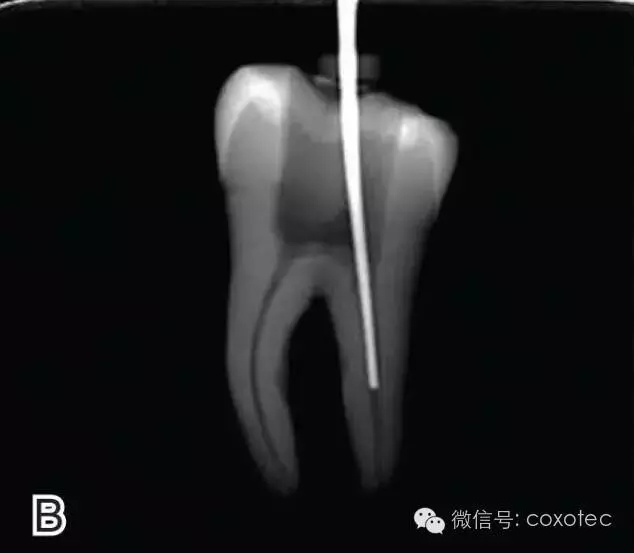

選擇非標(biāo)準(zhǔn)牙膠尖(如0.04、0.06 錐度牙膠尖)作為主尖,型號(hào)一般與根管預(yù)備最大號(hào)的器械型號(hào)一致,能到達(dá)距根尖0.5~1 mm 處,主尖尖段與根管壁緊密接觸。拍試尖X 線片進(jìn)行確認(rèn)(圖3)。

圖3 試尖,A.試主尖 B.拍試尖X片